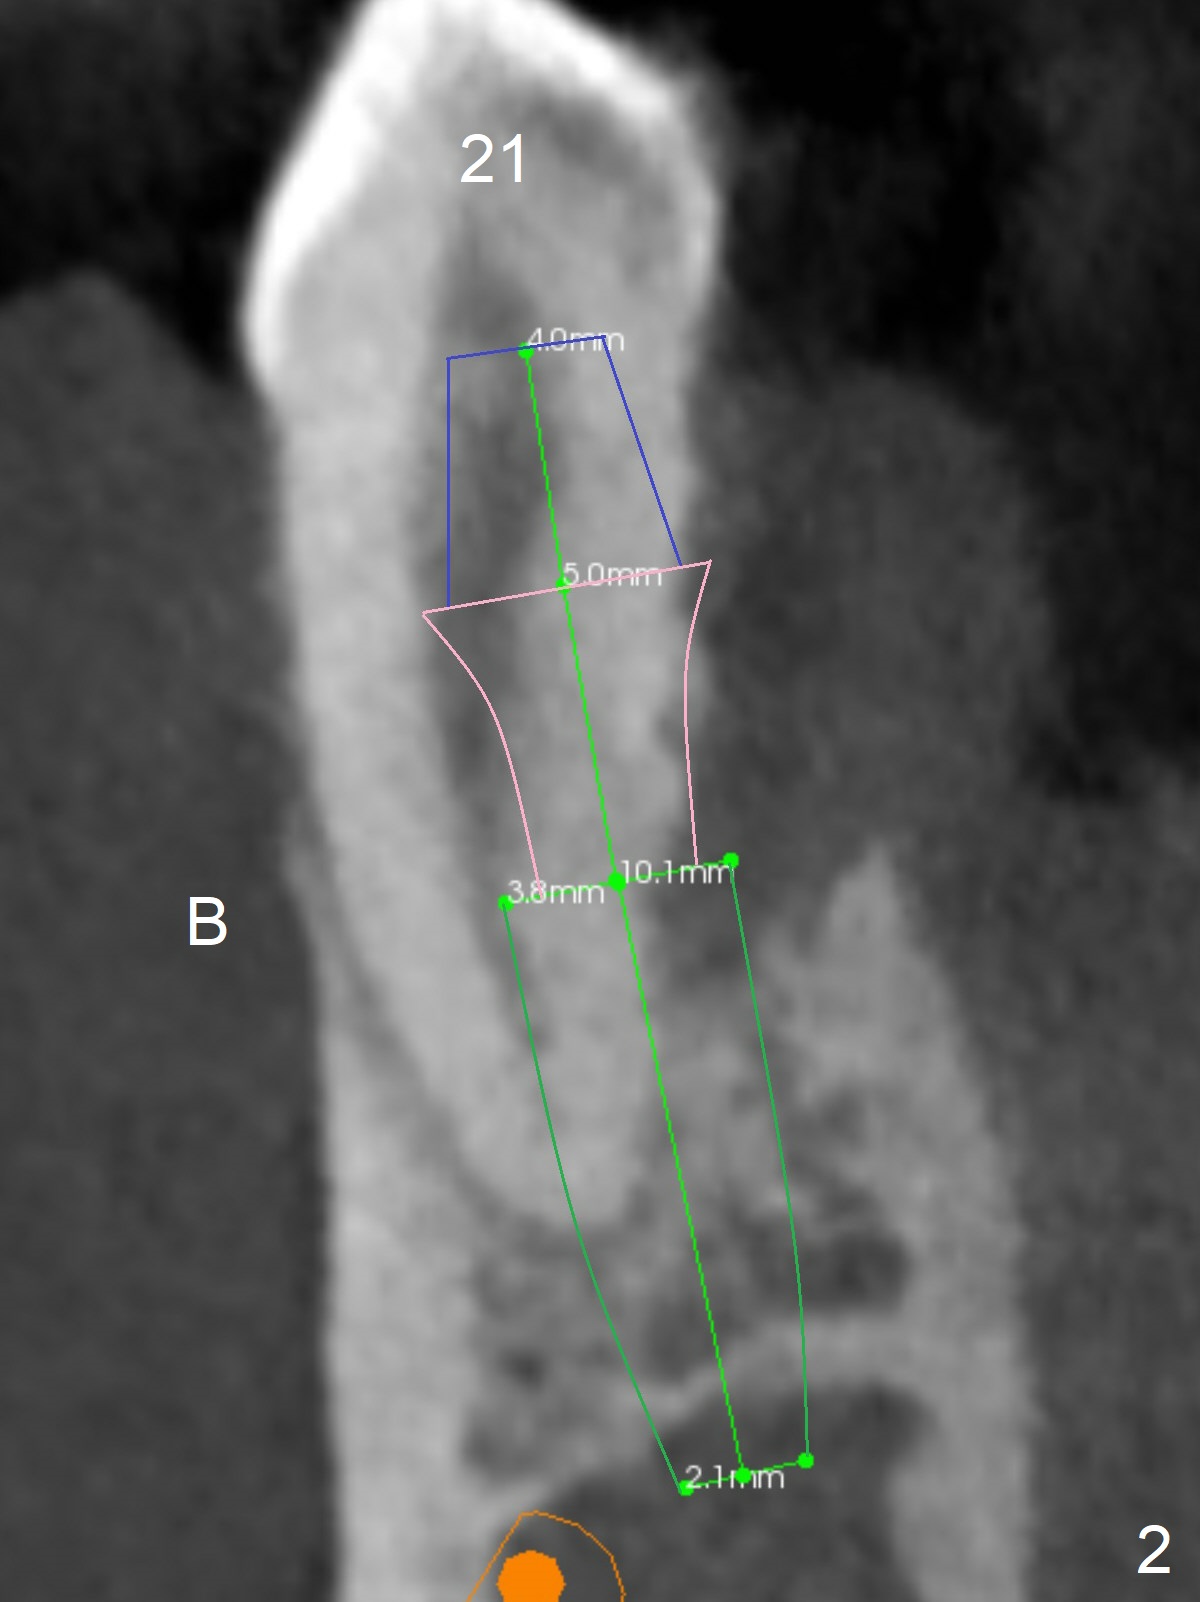

A 36-year-old man develops periodontal abscess at #19 and 20 after scaling & root planing. Since the site of #20 is close to the Mental Nerve, 3.8 mm tap or dummy implant will be used to form osteotomy instead of drills (Fig.1,3). While an implant will be placed in the middle of the socket #20, an implant will be placed as buccal as possible at #19 (Fig.4). If primary stability at #20 is poor, extract the tooth #21 and place a 3.8x10 mm lingually (Fig.2). PRF membrane will be placed prior to bone graft after implant placement (Fig.3 yellow).